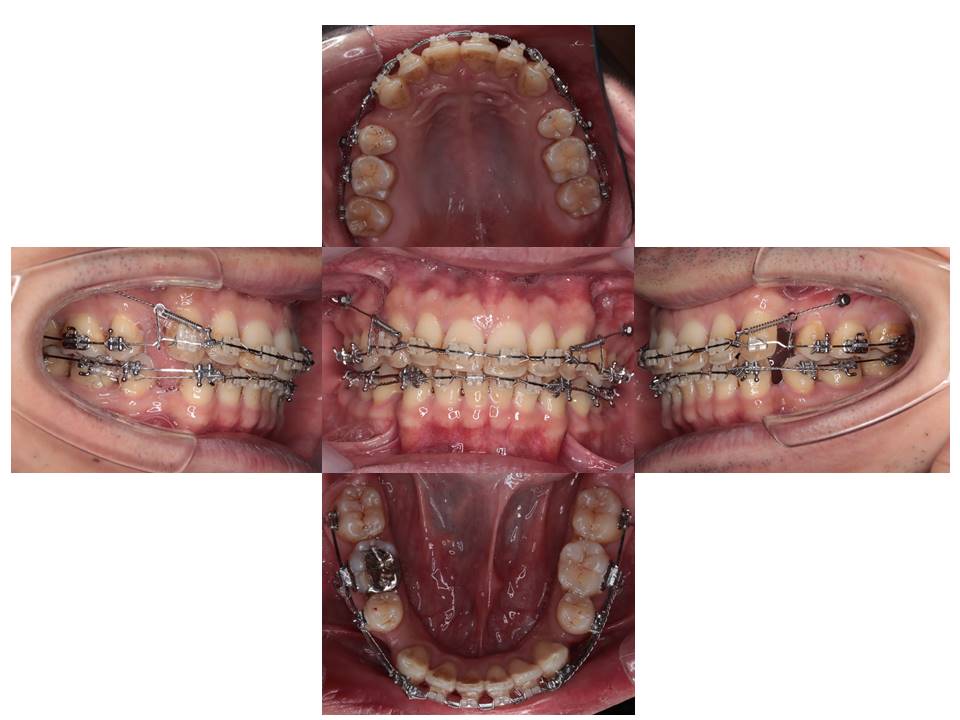

治療経過

上あごと下あごの歯列を並べています。

アンカースクリューを使用して上あごの前歯を後退させています。